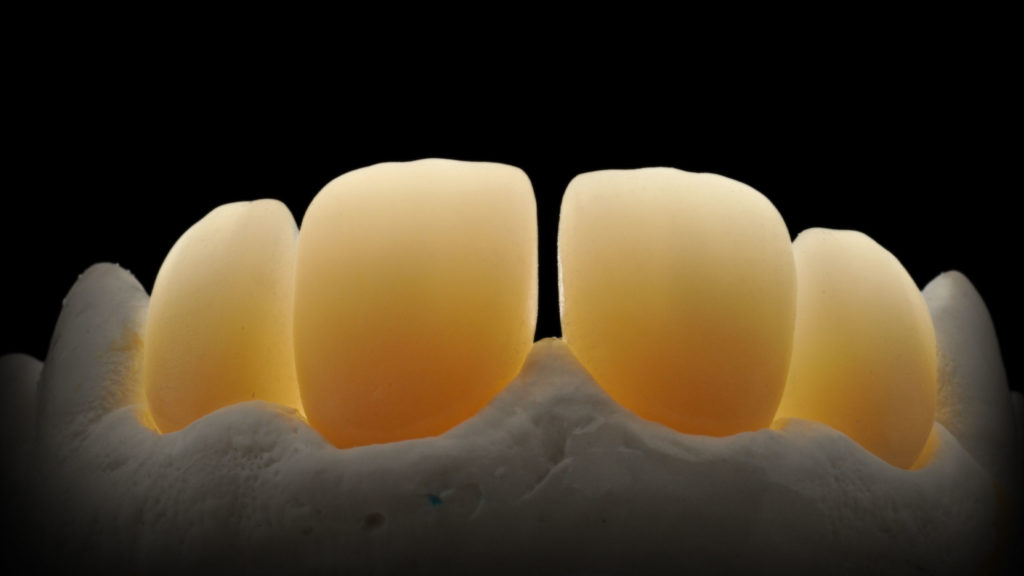

Bei mehrgliedrigen Lösungen und/oder wenn die ästhetischen Anforderungen nicht ganz so hoch sind (etwa im Seitenzahnbereich), ist es interessant, die guten Eigenschaften des neuen Katana Zirkonoxids zu nutzen und die geforderte hohe Festigkeit nicht außer Acht zu lassen. Für Fälle wie diese bietet es sich an, die gesamte Palatinalfläche vollanatomisch in Zirkonoxid zu belassen, und nur die Vestibulär- oder Bukkalflächen mit Luster-Massen in einer Art Einschichttechnik zu verblenden (Abb. 2).

Dentinkern mit Rückenschutz

Bei dieser Variante wird an einer vollanatomisch gestalteten Krone ein vestibuläres Cut-back vorgenommen. So verbleibt palatinal das monolithische Zirkonoxid, und vestibulär steht Raum zur Verfügung, um individuelle interne Charakteristika (etwa die Mamelons et cetera) mit einem Microlayering und Luster-Massen reproduzieren zu können (Abb. 6).